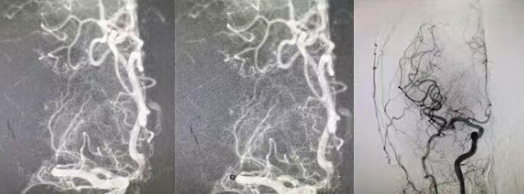

?近日,國(guó)文醫(yī)院門診超聲科成功為多位不明原因腦卒中及偏頭痛患者,開展了“右心聲學(xué)造影”檢查。此項(xiàng)新技術(shù)的應(yīng)用,標(biāo)志著我院在心源性卒中病因的精準(zhǔn)探查領(lǐng)域邁上新臺(tái)階,為眾多受“心病”困擾的患者帶來(lái)了更明確、更微創(chuàng)的診斷技術(shù)。 閱讀量:145